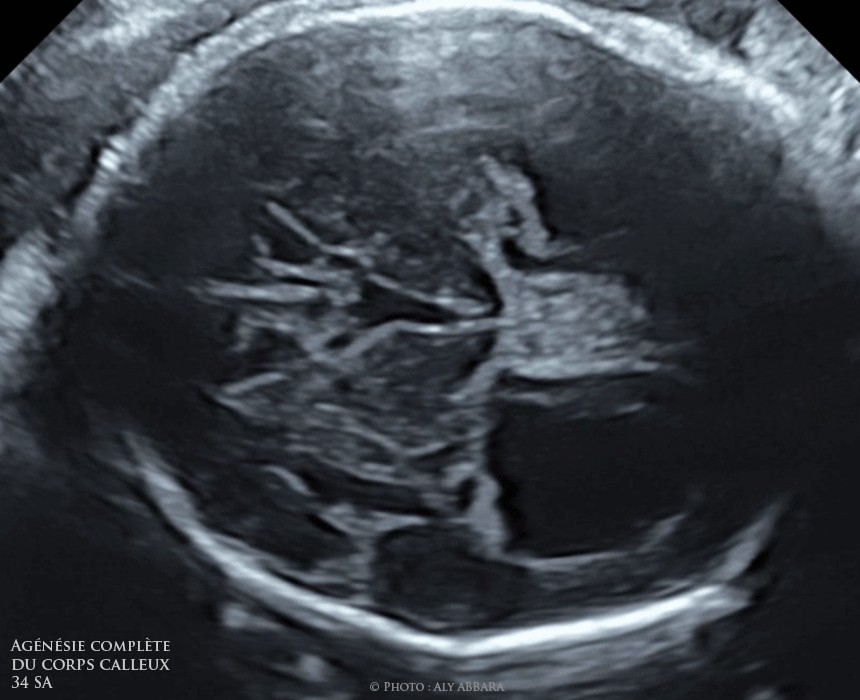

Agenesie Du Corps Calleux

Mon corps après bébé-Quand il existe chez un enfant, ou un adulte, des signes cliniques qui peuvent évoquer une anomalie du corps calleux quand un accident (traumatisme) ou une pathologie sans rapportSon absence, appelée l'agénésie du corps calleux, est une malformation cérébrale congénitale Rien ne remplace cette structure d'une dizaine de centimètres, hormis du liquide

Accueil du Forum Maladies neurologiques et musculaires Agénésie du corps calleux Le Forum maladies rares est un espace de partage d'informations et d'expériences pour lesLe corps calleux se développe in utero entre la dixième et la vingtième semaine de gestation L'agénésie du corps calleux est une malformation cérébrale congénitale dans laquelleEn agénésie primaire le

Parcourez 304 photos et images disponibles de corps calleux, ou lancez une nouvelle recherche pour explorer plus de photos et images cerveau xray (large) corps calleux photos et imagesLe diagnostic de ces deux affections est fait àL'agénésie du corps calleux désigne une malformation du cerveau consécutive à